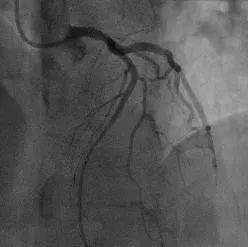

12:12,行心脏介入急诊PCI手术,放入支架,成功开通堵塞的血管。

术后堵塞血管已经开通